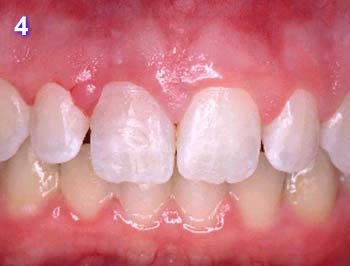

Este paciente se presentó con la queja principal de incomodidad en el funcionamiento de los dientes anteriores inferiores. Nótese la pérdida y recesión de encía.

La evidencia clínica de una enfermedad periodontal grave fue respaldada por las pruebas radiográficas en las que se observa una pérdida de hueso de más del 70% en los incisivos mandibulares y la presencia de un grado de movilidad 2 para los cuatro incisivos.